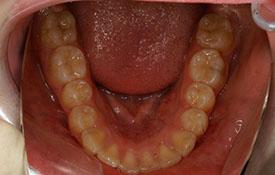

インビザラインの治療例:CASE-2

| プロフィール | 15歳 男性 |

|---|---|

| 所見 | アメリカから転院されて来られた方です。 インビザラインで上下顎の矯正治療を開始し下顎はアメリカで終了しており、上顎のみ治療の後期を担当しました。 アイライナーの装着は、1日平均22時間ほどでした。 |